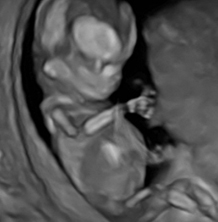

Die Möglichkeit, Ultraschallaufnahmen dreidimensional zu speichern, wird als 3D Technik bezeichnet. Dank sehr schneller Verrechnung dieser Bilder ist es möglich diese Bilder annähernd in Echtzeit wiederzugeben. Dann spricht man von 4D- Aufnahmen. Dieses Werkzeug nutzt der Pränataldiagnostiker, um Organe genauer untersuchen zu können (z. B. Gehirn). Wie bei einer Kernspinnuntersuchung können dreidimensionale Volumenblöcke gespeichert werden, die dann in der Nachschau beliebig gedreht und geschnitten werden können. In der Hand des Geübten ein großer diagnostischer Gewinn. Natürlich können auch Oberflächen (z.B. Gesicht) betrachtet werden, dies stellt jedoch nur einen kleinen Anteil an Möglichkeiten der 3D Technik dar.